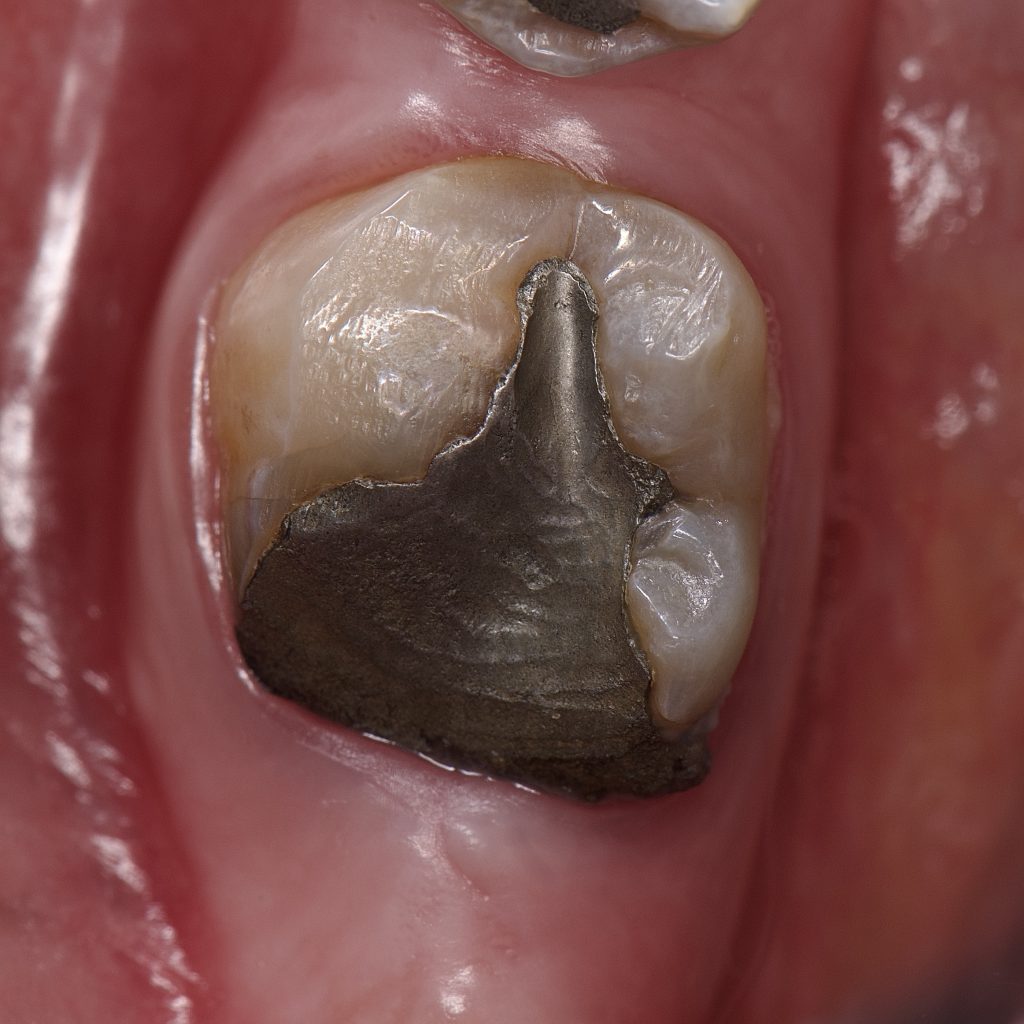

– Circumferential preparation done because the remaining enamel was carious mesially and demineralised buccally and lingually

– E max crown bonded with Heated Ap-x composite